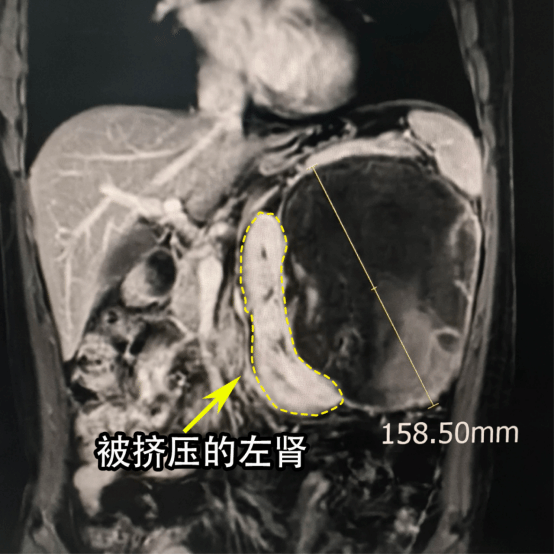

进一步检查后,情况比想象中更棘手。肿瘤直径有16厘米,而且是囊实性的,体积太大了,把左侧肾脏挤得完全偏离了原来的位置,一直推到了腹部正中间(图1).付德来副主任解释,这么大的肿瘤不仅压迫着周围的重要血管和脏器,还让手术难度陡增——既要完整切除肿瘤,又要保住肾脏,堪比在“刀锋上跳舞”。